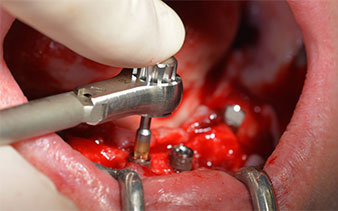

This corresponds to the next preset position in the Implantmed. Here we see the W&H contra-angle handpiece being held at a 45° angle to mesiocaudal in the region of 45 in order to preserve the mental nerve. The mental foramen is used as the anatomic reference for all drilling in this region. The subsequent holes were drilled at a reduced speed of 300 rpm (Fig. 10 and 11).

W&H contra-angle

Fig. 10